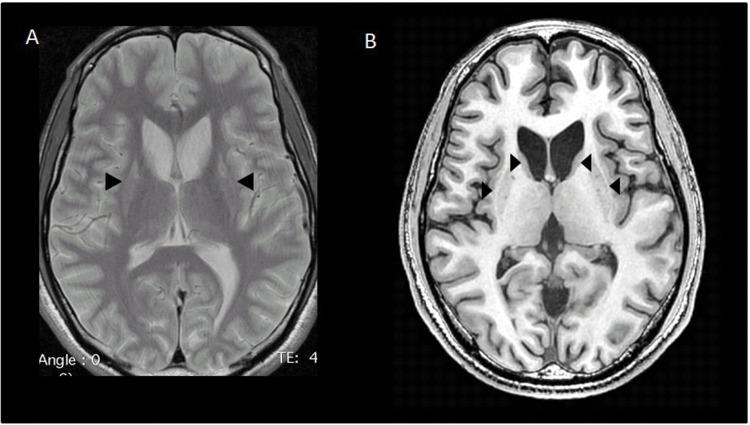

以成人起病的全身性肌张力障碍为主要表现的MEGDEL综合征

Adult-onset Generalized Dystonia as the Main Manifestation of MEGDEL Syndrome.

MEGDEL syndrome (3-MethylGlutaconic aciduria, Deafness, Encephalopathy, Leigh-like syndrome) is a severe neurometabolic disease with infantile onset.

PHENOMENOLOGY SHOWN

Progressive and marked dystonia over a 6-year period in an adult male with MEGDEL syndrome.

EDUCATIONAL VALUE

Generalized dystonia may be the main manifestation of a milder form of MEGDEL syndrome, which begins during adulthood.

MEGDEL综合征(3-甲基戊二酸尿症、耳聋、脑病、Leigh样综合征)是一种起病于婴儿期的严重神经代谢疾病。

表现出的现象

一名患有MEGDEL综合征的成年男性在6年时间里出现进行性且明显的肌张力障碍。

教育意义

全身性肌张力障碍可能是MEGDEL综合征较轻形式的主要表现,该形式始于成年期。